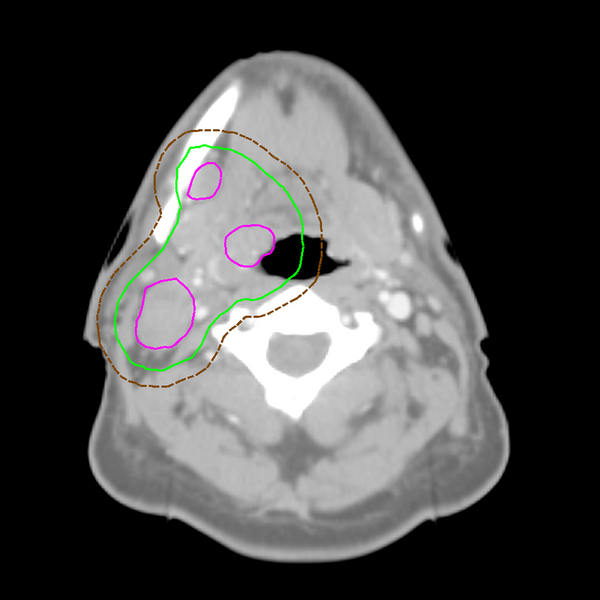

In this image, the purple lines delineate the GTV. Note how in this case, the GTV covers more than one area. The green line outlines the CTV, and the brown dashed line outlines the PTV.